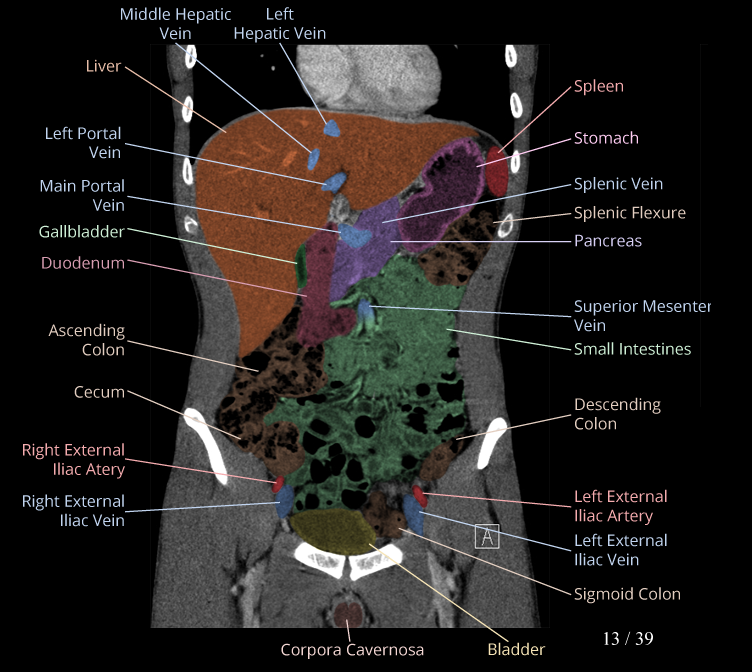

Body

Covers abdominal CT anatomy.